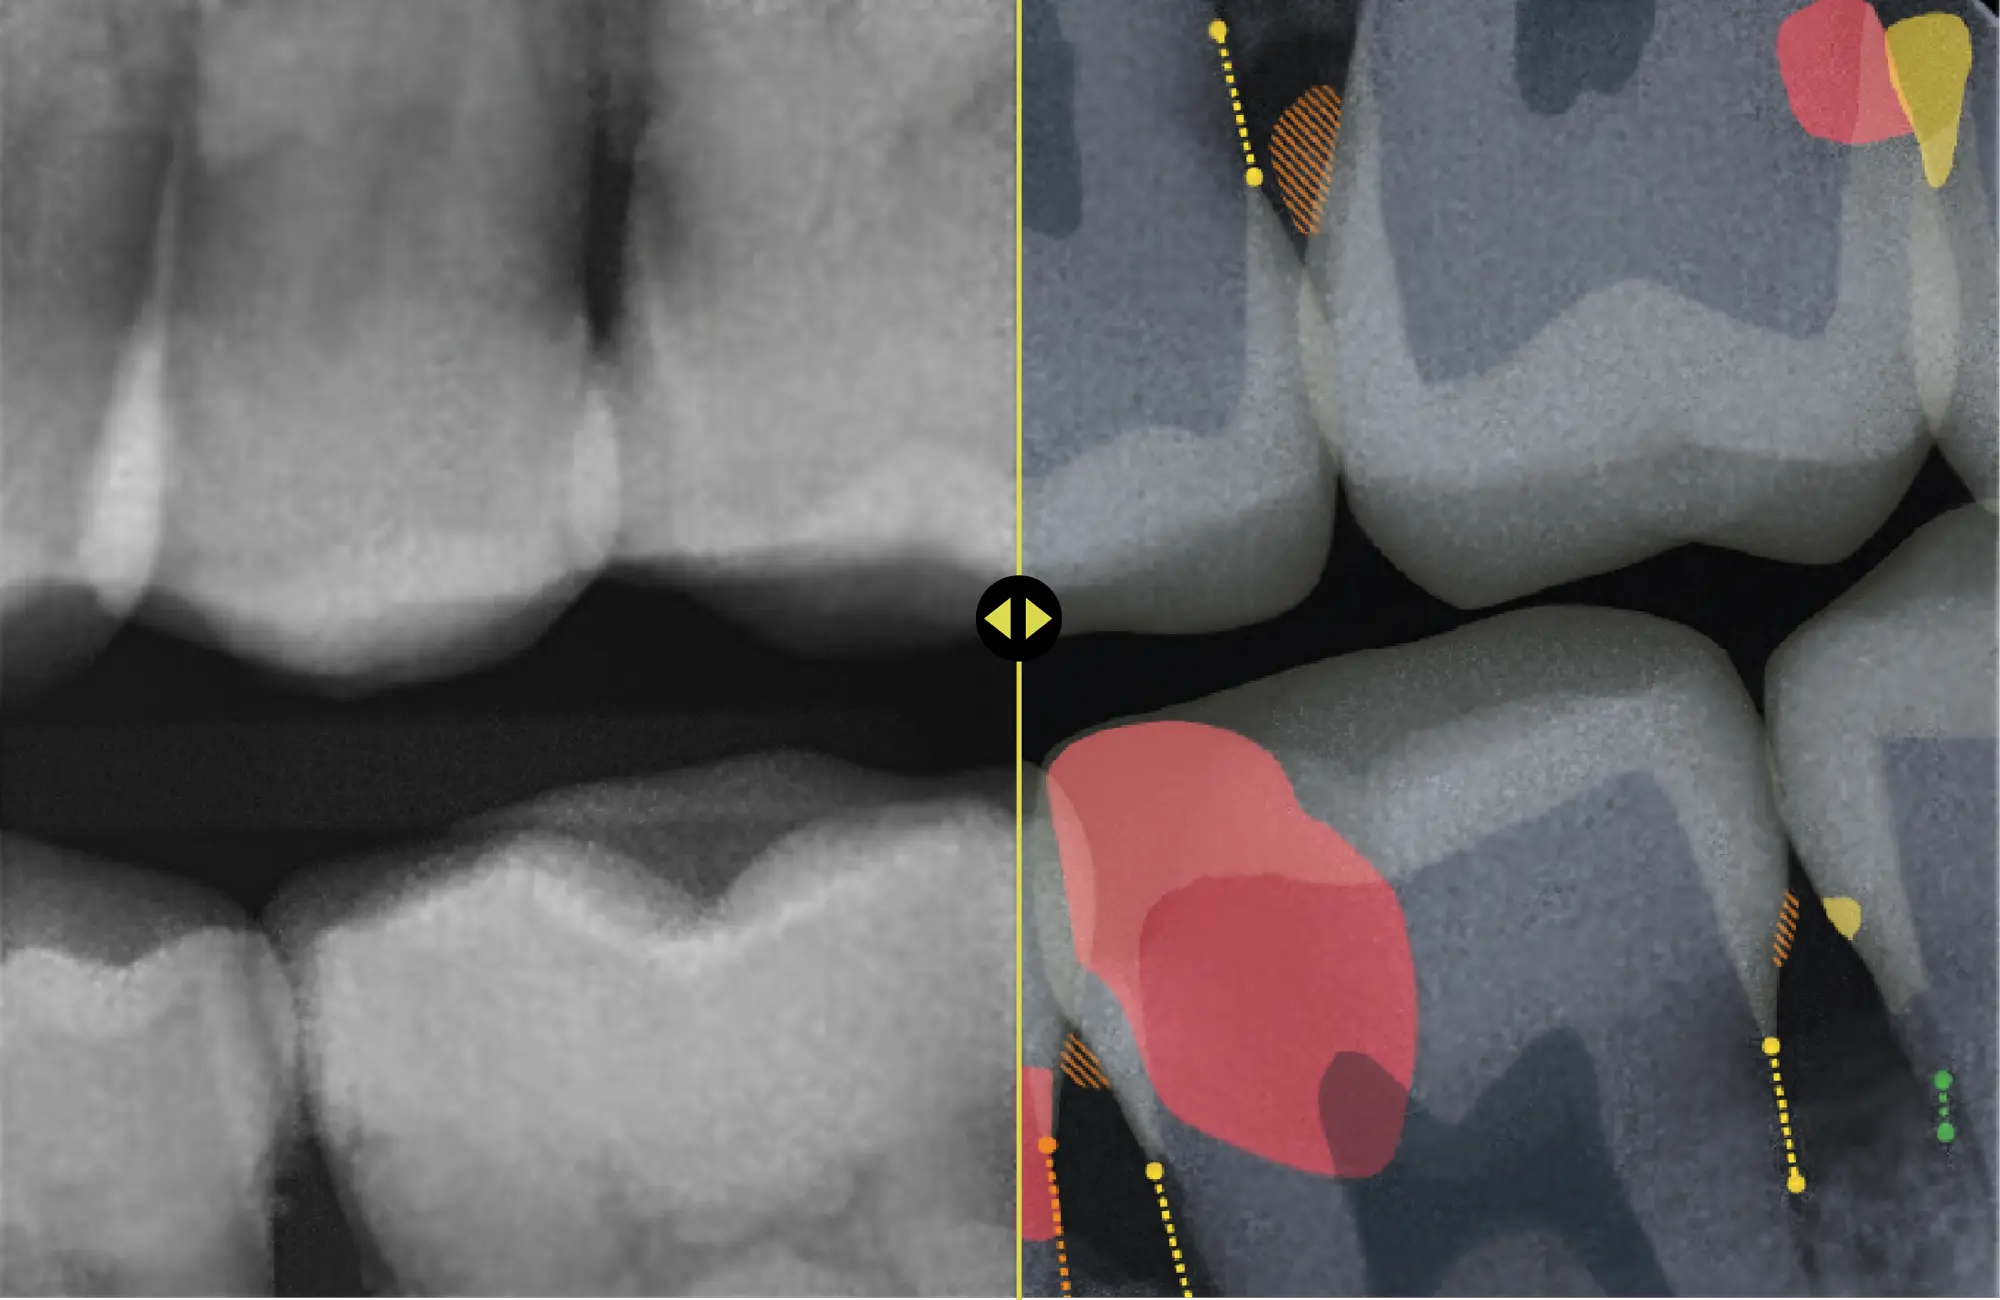

Clinical Assist from Videa turns X-ray findings into visuals patients can easily understand, so the conversation moves naturally from diagnosis to next steps.

AI analyzes X-rays in real time and highlights what needs attention.

Show patients exactly what you're seeing with visuals they can actually make sense of.